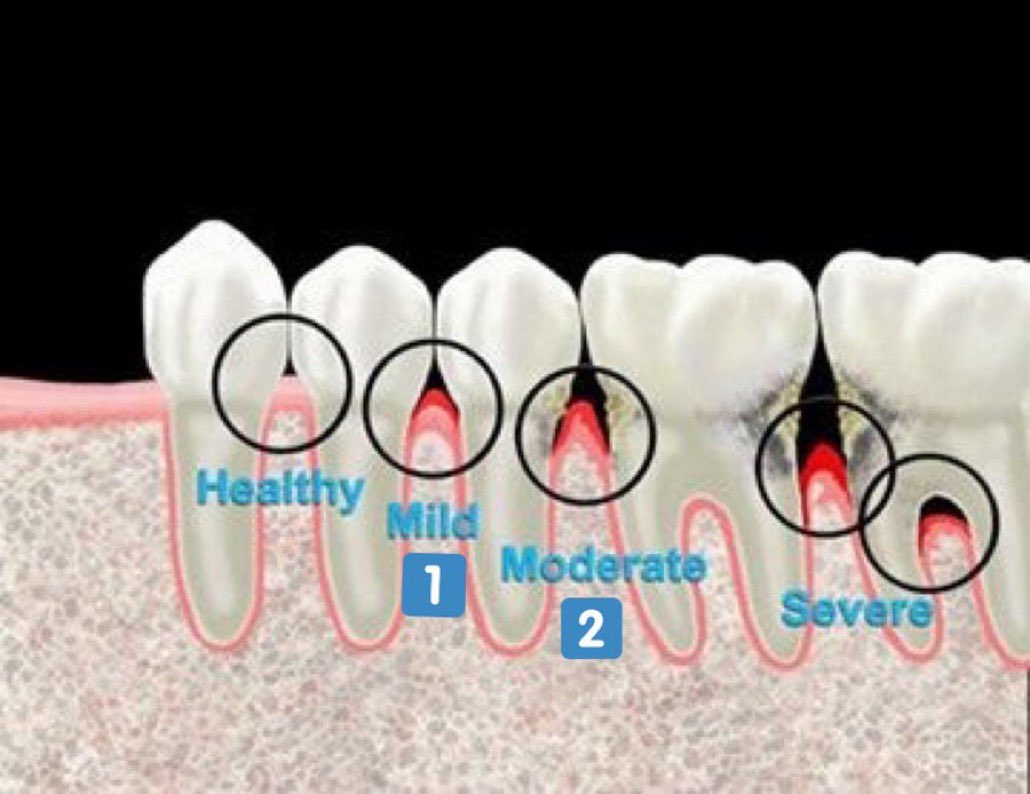

مراحل التهاب اللثة:

التهاب اللثة الخارجي(مرحلة١):

-الإنتفاخ

-الإحمرار

-النزف

-الألم

-سهل العلاج ويختفي تماماً

التهاب اللثة العميق(مرحلة٢):

-تآكل بسيط في اطراف العظم الداعم للآسنان وقد(غالبا)يكون مصحوب بعلامات من التهاب اللثة الخارجي

-يمكن علاجه إذا اكتشف باكرا وإيقاف تقدمه.(٣)=

-التهاب اللثة العميق (متوسط) (المرحلة ٣):

- بعض علامات التهاب اللثة الخارجية (ليس بالضرورة تكون موجودة)

-تآكل لمستوى اكثر في العظم الداعم

-نزوح في اللثة الخارجية (النسيج المحيط بالأسنان) (أحيانا)

-بدء حركة الأسنان بدرجة بسيطة

-يكتشف احيانا بالصدفة عند اخذ أشعة الأسنان(٤)=

لمرحلة المتقدمة من التهاب اللثة (المرحلة ٤):

-ألم ونزف

-حركة واضحة ومؤلمة عند المضغ

-رائحة كريهة ومزعجة

-سقوط الأسنان بدون التعرض لضربات أو حوادث

-العلاج قد يكون غير ممكن 💔 (٥)=